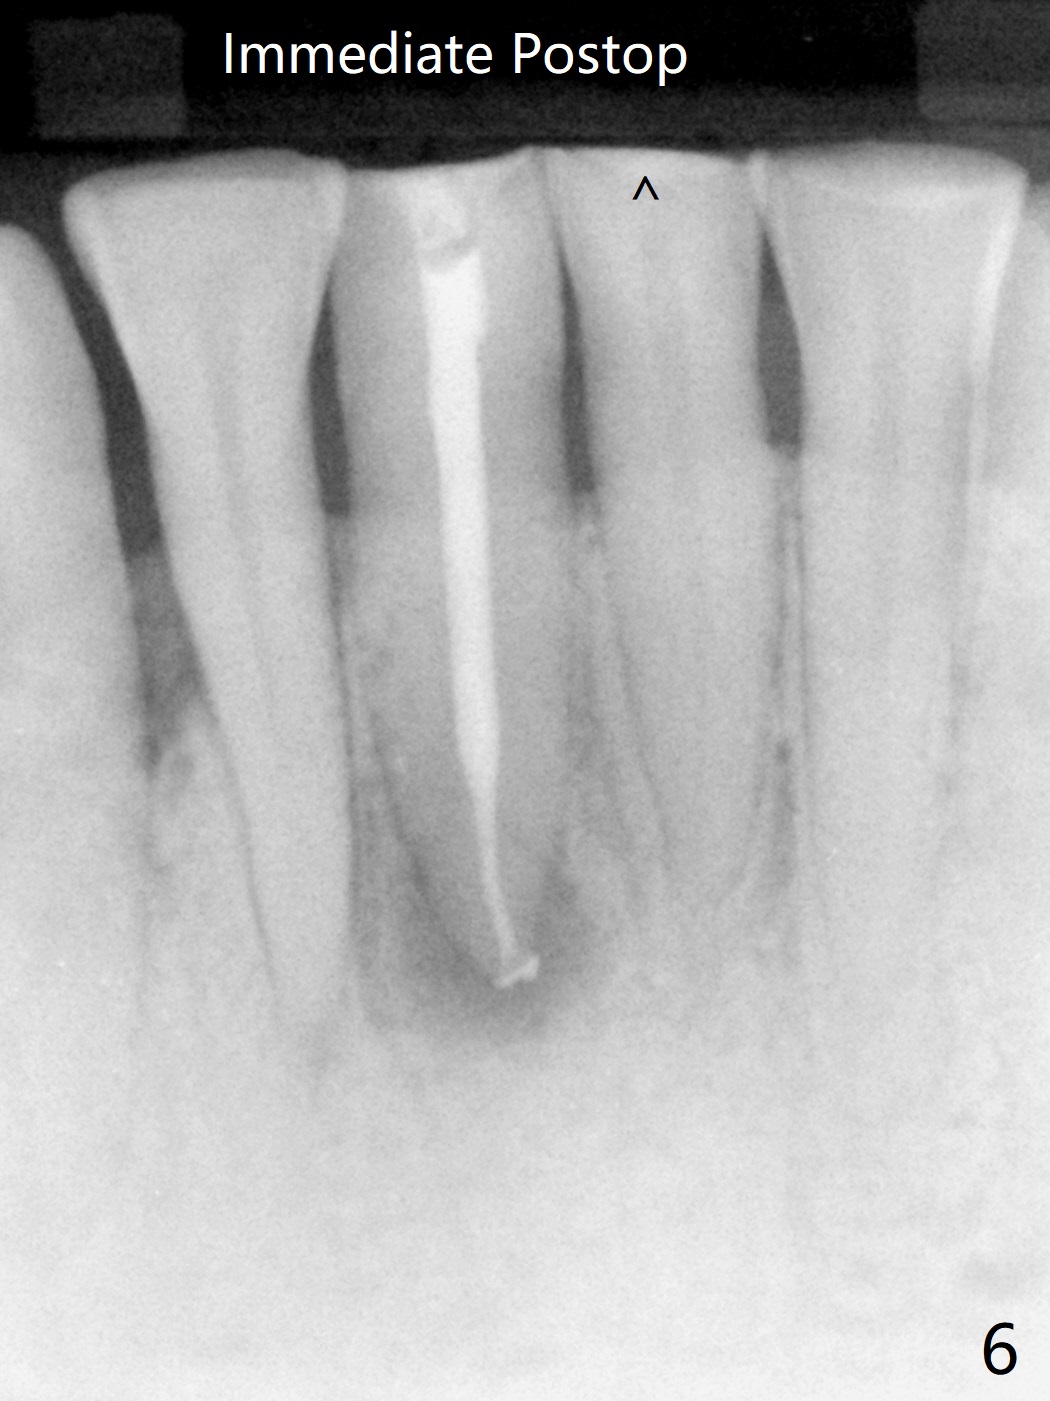

The tooth #24 is symptomatic with loss of incisal composite nearly 4 years postop (Fig.8 <).